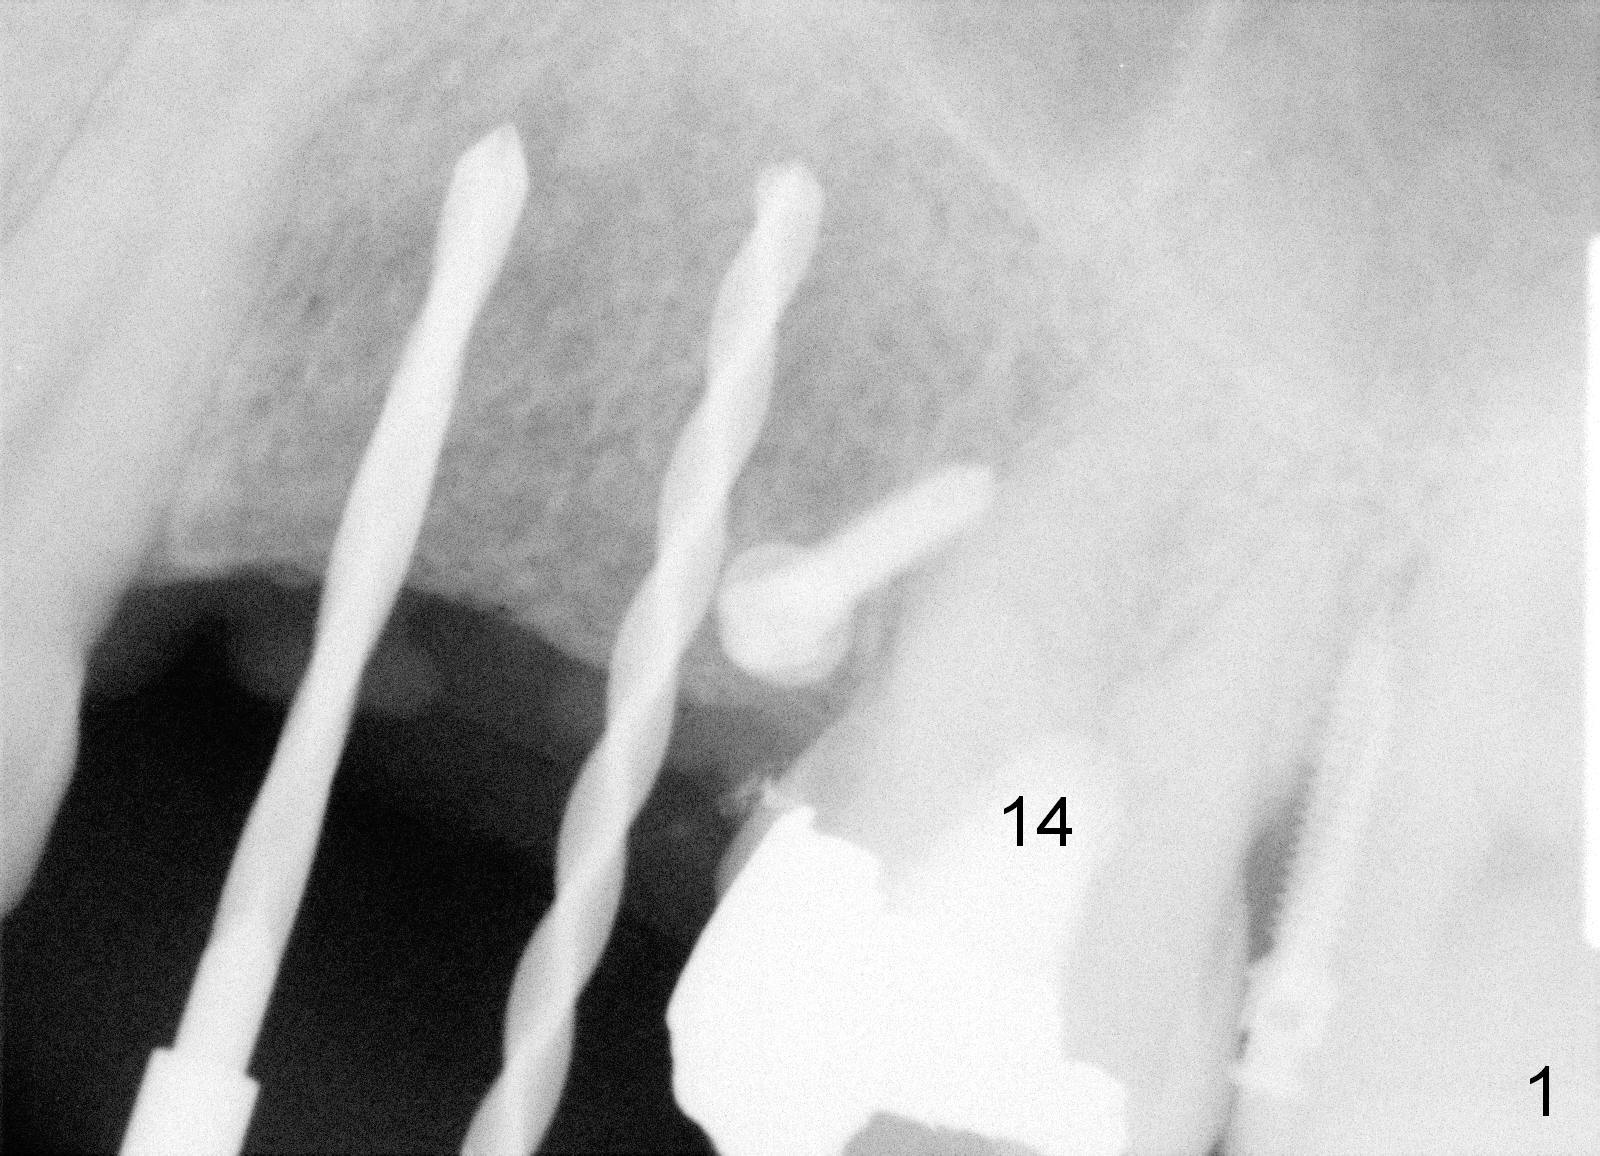

A 51-year-old man returns for #12,13 implant placement 2 years post extraction (Fig.1, 2 mm pilot drills 11 mm deep). Bone expanders are used (Fig.2 E), although the bone density is high. Two of 4x17 mm implant are placed with insertion torque > 60 Ncm (Fig.3). Four months postop, the implants are prepared for provisional as anchorage for limited ortho (Fig.4). When intrusion of #14 is finished, permanent crowns are fabricated for #12 and 13. Fig.5 is taken 1 year 1 months post cementation.